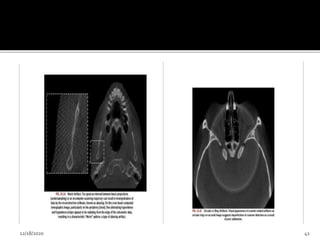

Cone beam effect-

• Is a potential source of artifacts, especially in the

peripheral portion of scan volume.

• Can result in

i. Image distortion

ii. Greater peripheral noise

• Clinically, the effect can be reduced by positioning

of ROI in the horizontal plane of x-ray beam.